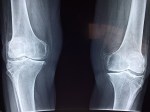

Clicking Knees:

Our knees take a lot of strain over the years, and they can be one of the most vulnerable places in our body to injury and damage. In particular, knees that click when you bend or move can be a sign that the cartilage inside them is wearing away. This can be a major issue because it means that over time the two bony parts of the knee joint will end up rubbing against each other without any cushioning which can cause serious pain and damage.

With that in mind, it is a very good idea to get painful or noisy knees checked out by a specialist at the first chance you get.